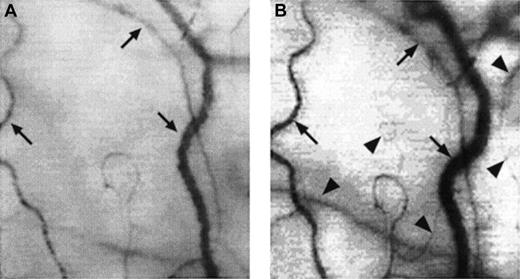

Two frame-captured images showing microvascular changes during crisis resolution in the same SCD patient.

Optical magnification, × 4.5; onscreen magnification, × 125. Focusing was aimed at the same location during crisis and crisis resolution, with the same vessel serving as its own reference baseline. (A) During crisis, there is significant reduction in vessel diameter and disappearance of capillaries and arterioles, resulting in extreme avascularity. The arrows point at the three vessels targeted for longitudinal comparison during crisis resolution. (B) An increase in vessel diameter and reappearance of capillaries and arterioles occur during crisis resolution. The vessels indicated by the arrows show a significant increase in vessel diameter. In addition, capillaries and arterioles (arrowheads) reappear during crisis resolution.